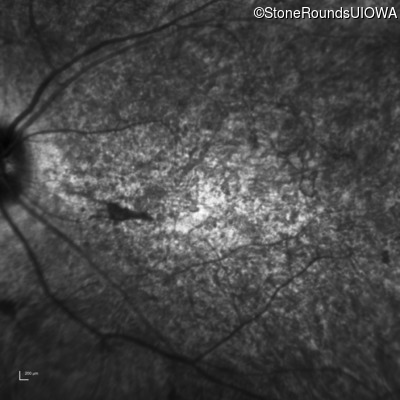

Infrared Fundus Photograph - Left - 20/250 sc

Exemplar